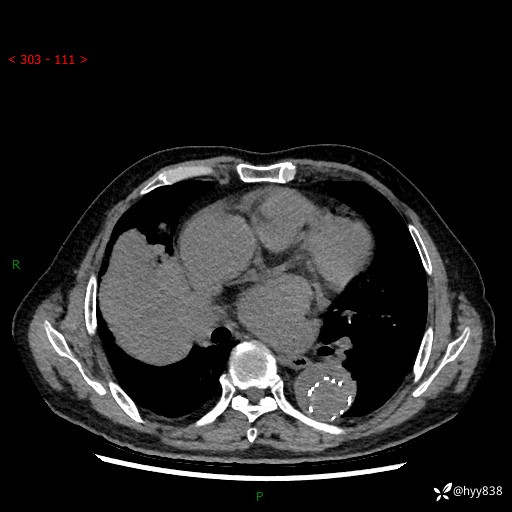

胸部CT平扫